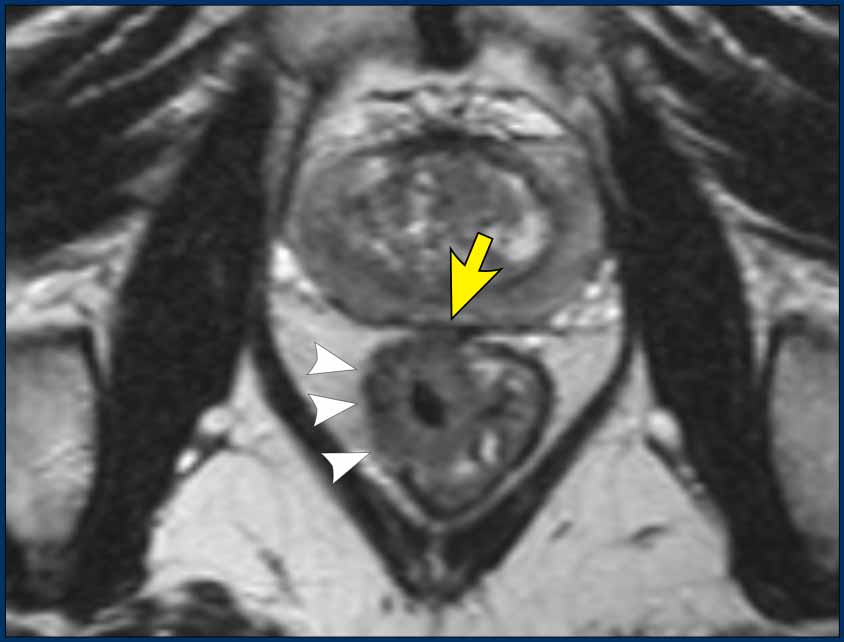

Signet-Ring Cell Rectal Adenocarcinoma

MRI Features

• Often challenging to identify

• Typically presents as long-segment, diffuse bowel wall thickening

• Submucosal growth pattern, yielding a "target" appearance on axial images

• Diffuse mesorectal fat infiltration is common

Images

The provided images demonstrate a signet-ring cell carcinoma with diffuse rectal wall thickening, the classic target appearance, and mesorectal fat infiltration.